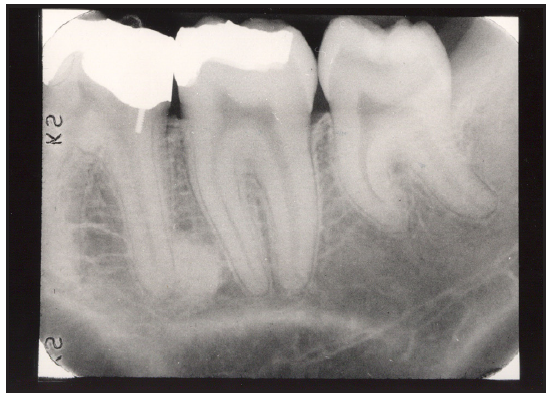

Bitewing examinations were introduced by Dr. Raper in 1925. Bitewing images focus on the clinical crowns of both the maxillary and mandibular teeth. Bitewings do not show the apices of the tooth and cannot be used to diagnose in this area. The greatest value of bitewing radiographic images is the detection of interproximal caries in the early stages of development, before it is clinically apparent. The arrows in Figure 2 indicate areas of interproximal caries. Bitewing images also reveal the size of the pulp chamber and the relative extent to which proximal caries have penetrated.

Bitewings also provide a useful adjunct to evaluating periodontal conditions. They offer a good view of the septal alveolar crest, and in addition, permit changes in bone height to be accurately assessed by comparison with adjacent teeth.